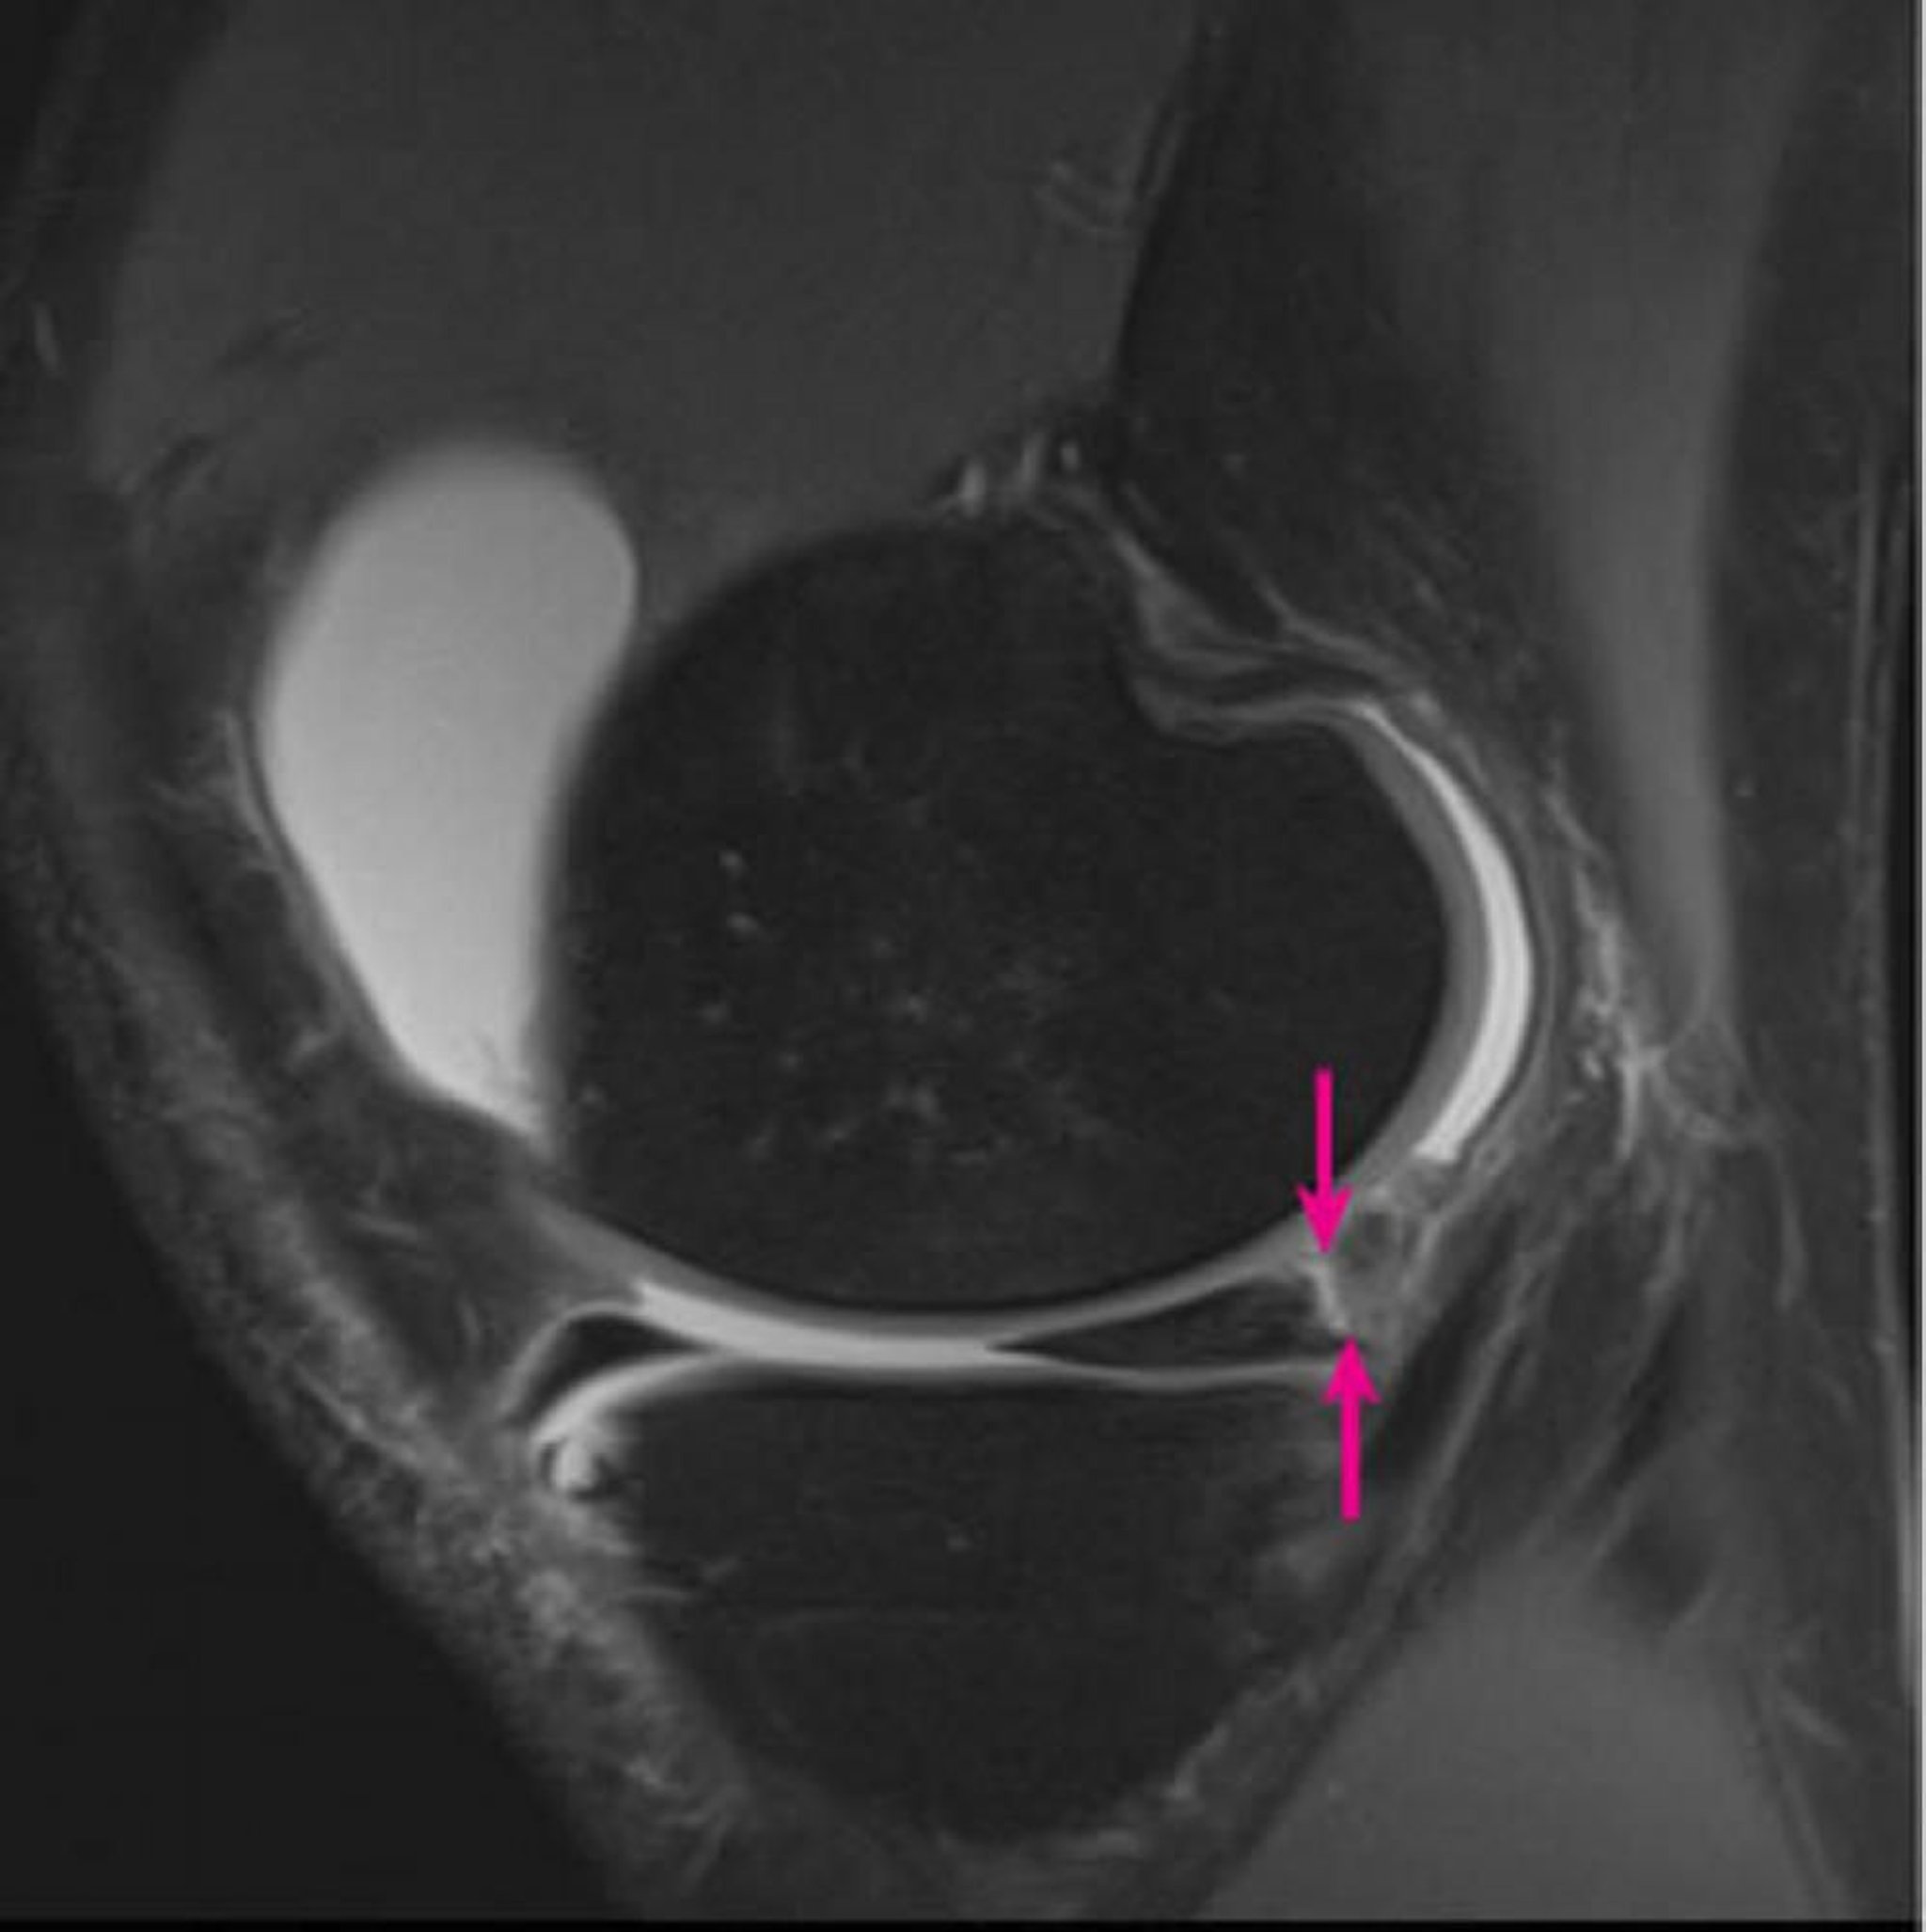

L'immagine alla RM 3-tesla pesata in protone sagittale del ginocchio destro mostra la separazione meniscocapsulare che coinvolge il corno posteriore del menisco mediale (frecce).

Image courtesy of Hakan Ilaslan, MD.